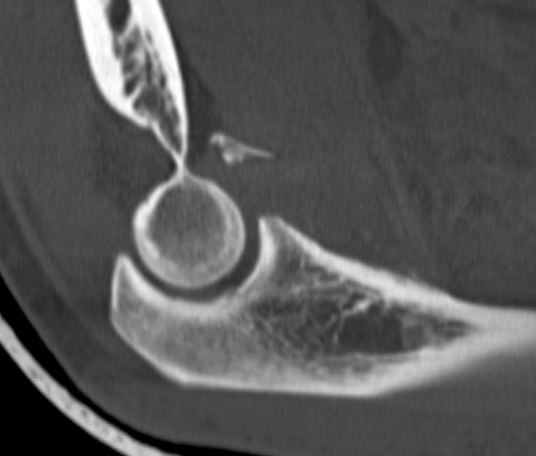

O'Driscoll classification anteromedial coronoid facet fractures

| Type I | Type II | Type III |

|---|---|---|

| Transverse fractures | Anteromedial facet fractures | Basilar fractures |

| Lasso suture fixation |

Lasso suture fixation - small Medial buttress plate - large |

Dorsal +/- medial plate |

Anteromedial coronoid facet fragment

- associated with varus posteromedial rotational force

- associated with tear of lateral ulna collateral ligament (LUCL)

- systematic review of anteromedial coronoid facet fractures

- 6% Type I, 62% Type II, 32% Type III

- 73% fixed with buttress plate

- 70% LUCL fixation